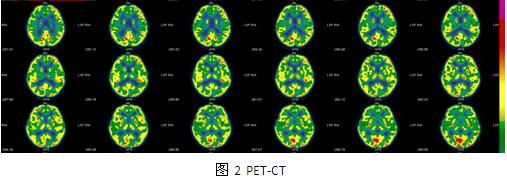

入院后检查:血常规、肝肾功能、离子、凝血、传染八项结果正常。心电图、腹部彩超、心脏彩超、胸片未见异常。韦氏全量表83,言语83,操作87,记忆86。头颅CT结果示:左侧顶枕及侧脑室周围多发钙化,左侧顶枕为著。头颅MR结果示:大脑皮层多发异常信号,考虑结节性硬化(图1)。视频脑电图示:异常脑电图Ⅲ(清醒/睡眠),间歇期:癫痫样放电,弥漫性,双后头部著;发作期:临床:强直(轴-肢带型),EEG:发作型,弥漫性,双后头部著。PET:左侧枕叶内侧面代谢明显减低(图2)。入院诊断:

讨论:患者发作间歇期及发作期均为双侧弥漫性放电,但后头部明显,考虑局灶性癫痫,患者颅内多发病灶,考虑症状性局灶性癫痫,患儿有皮肤色素脱失斑,影像学有脑皮层发育不良,符合2012年结节性硬化专家共识的结节性硬化诊断标准。患者多种抗癫痫药物无效,考虑外科手术治疗,有研究表明:钙化结节和最大结节很有可能是结节性硬化患者的致痫结节,手术切除能取得良好手术效果,儿童脑发育不完善,局灶性癫痫往往以全部性发作为表现形式,患者发作形式为强直发作,是以全部性发作为表现的局灶性癫痫,结合VEEG、PET-CT最终予左枕内侧面结节切除,术后取得良好的效果,相关文献研究显示:儿童后头部癫痫的症状学,显示了重要的年龄相关性,与成人相比,儿童发作时间更短但更频繁,很少有先兆或视觉感觉症状,偶发复杂运动及全身强直阵挛,而发作微笑,点头和行为改变是典型的特征,强直发作的患者中(SPECT)检查结果在额叶辅助运动区(SMA)的高灌注,考虑后头部癫痫向前传导至SMA可能,还需进一步证实。